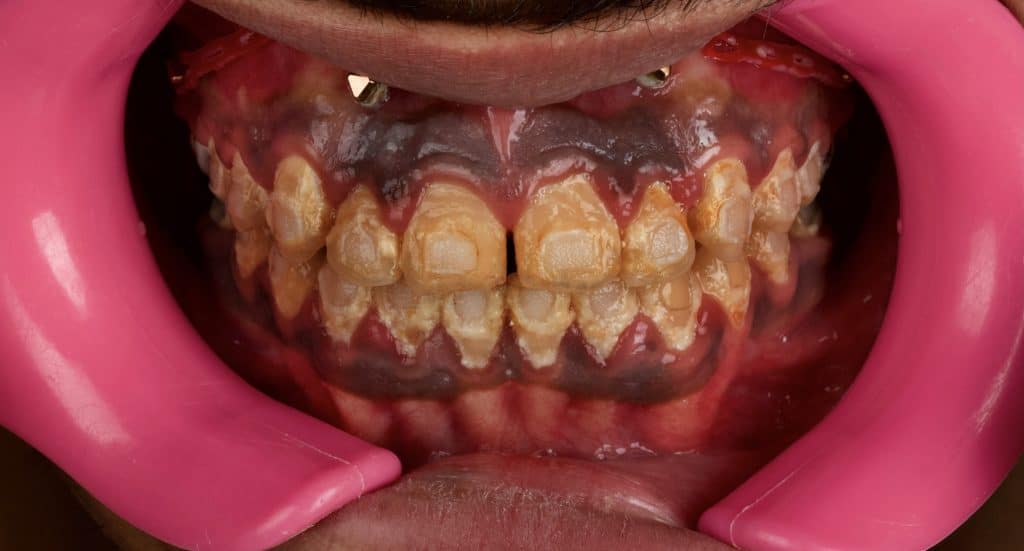

Initial situation

Scaling then after 3 days laser gingivectomy, dipigmentation and frenectomy after one week removal of carious endodontic treatment cause of pathological exposure , post and core build up reduction after one week finishing reduction and impressions